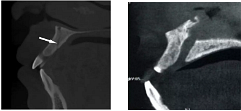

(3)相鄰解剖結(jié)構(gòu)

血管(白色箭頭)、鼻腭管(右圖)